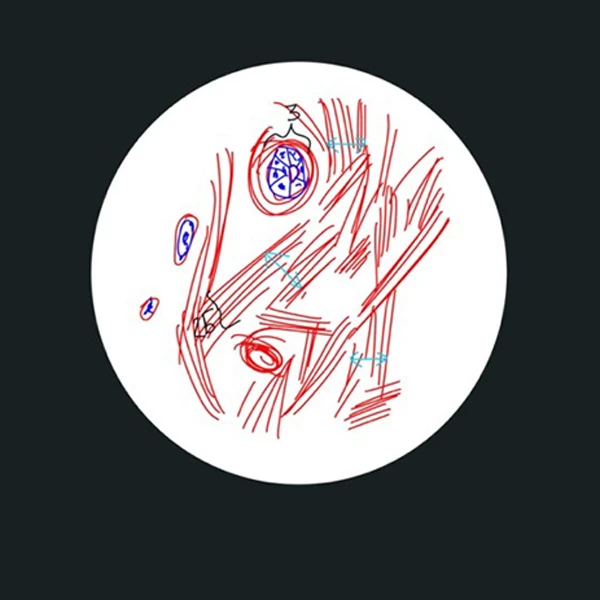

Рис. 2. Виды соединительной ткани в панч-биоптате после курса сеансов воздействия, окраска гематоксилин+эозин: кровеносные сосуды-капилляры (3), строго ориентированные пучки волокон (2Б) в стромальных трабекулах и большое количество активных фибробластов (2А). Голубыми стрелками указаны длины просвета сосудов.

Косвенно это подтверждается второй группой зафиксированных изменений на фоне применения аппарата Beautylizer (RSL-скульптурирование*): увеличении просвета сосудов микроциркуляторного русла на единицу площади зоны, что свидетельствует об активации не только функциональной части микроциркуляторного русла, но и стимуляции работы как коллатерального кровообращения, так и основного. Активное кровоснабжение позволяет не только снизить задержку жидкости в тканях и формирование отеков, но и простимулировать активную работу клеток, продуцирующих полезные белковые компоненты соединительной ткани3.

Третьей группой обнаруженных изменений является увеличение междольковых перемычек4, что, вероятно, указывает на снижение фиброзирования данных септ. Помимо функционального значения, эта группа несет ярко выраженный визуальный эффект в виде уменьшения выраженности «апельсиновой корки».